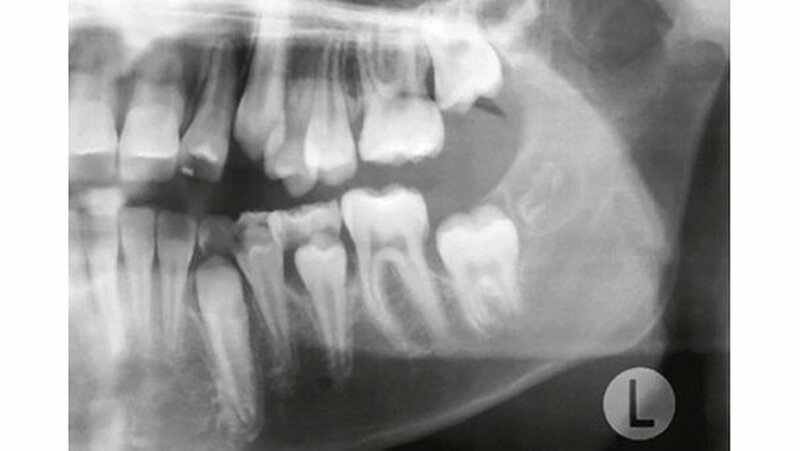

Auf dem mitgelieferten vier Jahre zuvor erstellten Orthopantomogramm (OPT) waren noch keine Hinweise auf das Vorhandensein einer Veränderung regio 32-34 sichtbar (Abbildung 2). Ein Jahr später konnte anhand des OPT bereits eine radioopake Struktur regio 33, 34 festgestellt werden (Abbildung 3). Auf dem aktuellen OPT und digitalen Volumentomogramm (DVT) zeigten sich regio 32-34 lingual multiple, rundliche, unterschiedlich große Radioopazitäten, umgeben von einer radioluzenten Zone.

Die Ränder der radioluzenten Zone waren sehr gut zum umgebenden Alveolarknochen abgrenzbar (Abbildung 4, 5). Eine dreidimensionale Diagnostik (DVT) macht aus dreierlei Gründen Sinn: 1. Erleichterung der Patientenaufklärung, 2. optimale Lagebestimmung des Tumors in Bezug zu benachbarten anatomischen Strukturen wie Nachbarzähne und Nerven, 3. präoperative Bestimmung der Anzahl zahnähnlicher Strukturen (zusammengesetztes Odontom), um kontrollieren zu können, ob während des operativen Eingriffs alle hartgewebigen Tumoranteile entfernt worden sind.